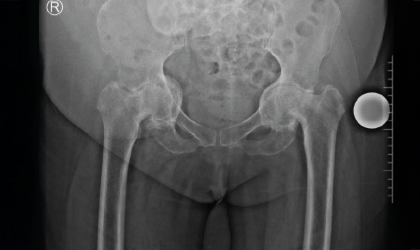

This 68 year old lady has a condition called protrusio where the socket becomes weak and protrudes into the pelvis. She was on a wheel chair for over a year with two caretakers to care for her. She needed very complex hip replacements which required a lot of planning. We had to bone graft the socket as well. The hip replacements have made her independent and painfree. Now she walks without support.

Patient Outcome

The patient is now pain-free and walks without any support. She has transitioned from complete dependence to full independence, significantly improving her quality of life.